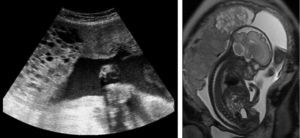

A las 20,5 semanas de amenorrea se realizó el primer control del embarazo y ecográficamente se sospechó una gestación gemelar con una mola hidatiforme completa y un feto vivo morfológicamente normal, que se confirmó por resonancia magnética (fig. 1).

Para concluir, queremos señalar que la ecografía puede identificar una gestación gemelar donde coexistan una mola y un feto normal. La resonancia magnética pude aportar imágenes que complementen el diagnóstico de esta entidad. El diagnóstico de esta entidad presenta dilemas importantes para la madre, que debe enviarse a un hospital terciario para control de la gestación por el alto riesgo de complicaciones maternas y fetales.